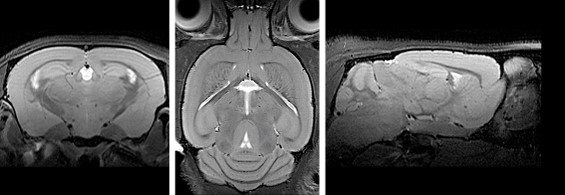

Dem Gehirn beim Arbeiten zuzuschauen, ist dank Magnetresonanztomographie (MRT) ohne Eingriff von außen möglich. Am 27. und 28. September wird am Magdeburger Leibniz-Institut für Neurobiologie (LIN) ein neuer 9,4-Tesla-Kleintierscanner offiziell eingeweiht. Das Gerät ermöglicht Aussagen über Veränderungen der Hirnstruktur, des Stoffwechsels und der regionalen Gehirnaktivität, die sich gut mit MRT-Befunden am Menschen vergleichen lassen und somit auch zur Erprobung diagnostischer Verfahren dienen können.

Mit 9,4 Tesla beträgt das Magnetfeld des Gerätes das 200.000-fache des natürlichen Erdmagnetfeldes – und ist damit dreimal so hoch wie das Magnetfeld in üblichen Klinik-Geräten, was deutlich detailreichere Einblicke in das arbeitende Gehirn bedeutet. Dank der modernen MRT-Technik können Bilder von der Struktur des Gehirns erzeugt werden, die Verteilung von biochemischen Stoffen kann dargestellt werden und sogar die Hirnaktivität beim Denken, Fühlen oder Entscheiden kann mit diesem Verfahren sichtbar gemacht werden.